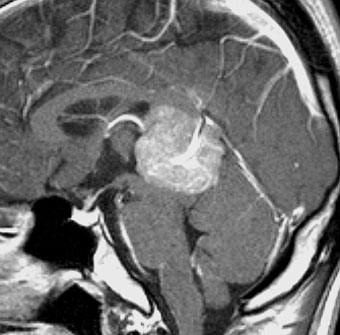

軽度の複視のみで発症した20代前半男性です。右上のように松果体腫瘍の前に割れ目が入るように第3脳室があり,両側視床に浸潤するために軽度の視床浮腫があり,ガドリニウムで強く増強され一部にのう胞があります。これだけでもgeriminomaにかなり特有の所見です。さらに,灰白隆起(矢印)のところに小さな神経下垂体germinoma腫瘍があります (bifocal tumor)。HCGは測定限界以下,AFP 2.5で,水頭症はありません。全ての臨床所見がgerminomaであることを示しています。

生検病理診断をしないでICE化学療法を1コース終えた後の画像です。腫瘍は消失しています。これでgerminomaであることが確認できたので,ICE化学療法を2コース追加して,25.2グレイの全脳室照射をして治療を終了しました。